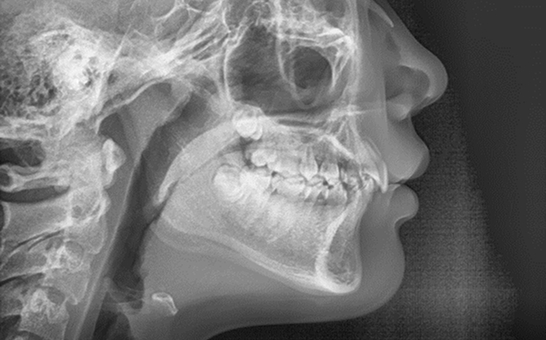

디지털 기반의 시뮬레이션 진단 과정을 통해 치아의 배열, 턱 관절 상태,

교합 상태를 정밀히 분석 후 교정 치료 계획을 수립하여 복잡한 케이스,

어려운 고난도 케이스도 전문적인 교정 치료가 가능합니다.

단순히 치아 배열만 보는 것이 아니라, 교합 상태, 치아 마모,

교정 필요성까지 정밀 분석이 가능합니다.

치아와 교합 상태를 정밀하게 분석하여

환자에게 맞는 인비절라인 치료 설계가 가능합니다.